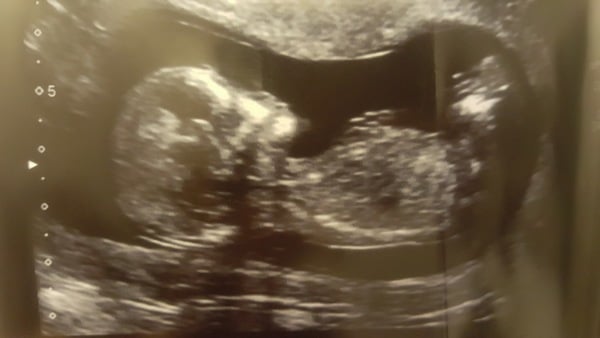

Can't belive I forgot to post my scan pic! Can't wait to see him/her again

Such a good pic daisy mine are all just blurs!

Lovely scan picture Daisy!!

Lovely pic Daisy! I can't wait for my next scan either. Got 20 week scan on 8th Feb.

Daisy lovely scan pic. I can't wait for my 20 wk scan on 10th Feb. it feels like an age away. When do people start showing. I swear my belly has shrunk. The only sign that I am pregnant is that I feel nauseous and bloated after eating lunch and that feeling carries on till bedtime.